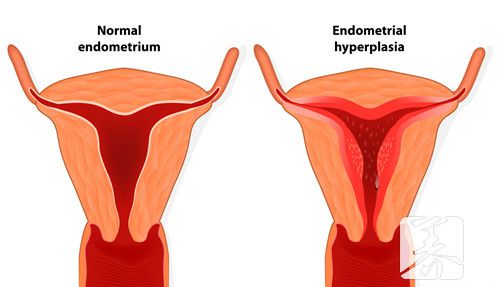

宫腔分离是女人子宫中产生的一个症状表现,许多女士做宫腔内查验的情况下都是显示信息宫腔分离的状况。一些女性检查数据显示宫腔分离2mm,由于不明白医学常识,因此就很困惑,那麼宫腔分离2mm是什么含意?

在为大伙儿答疑解惑这一问题的情况下,首先来跟大伙说说宫腔分离代表什么意思吧。实际上宫腔分离是一种b超检查的专业术语,多表明女士子宫腔有积血积血或残留。有的人可能会觉得沒有做了人流手术,子宫体内就不容易有残余,但大伙儿要了解月经后,子宫壁沒有彻底脱离,也非常容易导致这类状况的。

一切正常状况女士子宫壁是粘在一起的,假如b超显示信息宫腔分离2mm,那麼这就表明子宫腔有积血、血液、浓液等变病,进而造成 宫腔分离。在这类状况下,要融合临床医学开展剖析,如果是绝经后出現宫腔分离,并伴随下腹部疼痛,有些人还会继续出現体温升高的状况,那样的话就可能是子宫腔积脓导致,需要做宫颈扩大实际操作将浓液排出来。

人流手术后宫腔分离2mm,意思是子宫腔两mm的积血沒有所有清除宫腔内,多是孑宫修复欠佳引发,可以吃协助宫缩的药品开展医治。